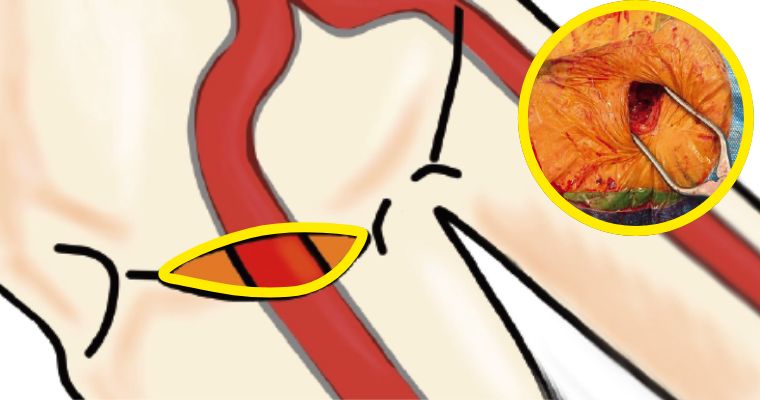

主に一箇所のバイパスを行う場合に有用な方法です。小さい傷で行う場合、内胸動脈を採取が困難となる問題があります。カメラを用いない直視法では、視野が悪い為、傷が大きくなりさらに肋骨の間を器具で大きく広げるために、疼痛や美容的な問題があります。3D内視では広い範囲の動脈を小さい傷で採取できる為、これらの問題を解決できる利点があります。ただし、内視鏡採取は豊富な経験が必要な為、全国的にも限られた施設でしか行っておりません。

吻合は傷を痛めないように組織に優しい器具を用いて行います。

この方法を基本として、複数の血管へのバイパス手術を行っています。